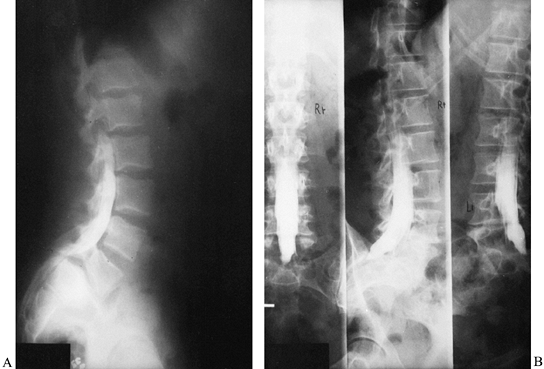

resection, instrumentation, and reduction of L-4 onto S-1. As in other

forms of spondylolisthesis, the severity of clinical symptoms in

patients with spondyloptosis does not necessarily correlate with the

degree of subluxation. Thus, L-5 vertebrectomy and reduction are

advised only for severely disabled patients (Fig. 162.11).

![]() |

|

Figure 162.11. A: Preoperative lateral radiograph of a 42-year-old man with spondyloptosis and debilitating back and leg pain. B: Preoperative myelogram shows total blockage. C: Lateral radiograph after first-stage L-5 anterior vertebrectomy. D:

Lateral radiograph after second-stage reduction of L-4 onto the sacrum and pedicle-screw fixation. Alignment and lordosis have been restored. |